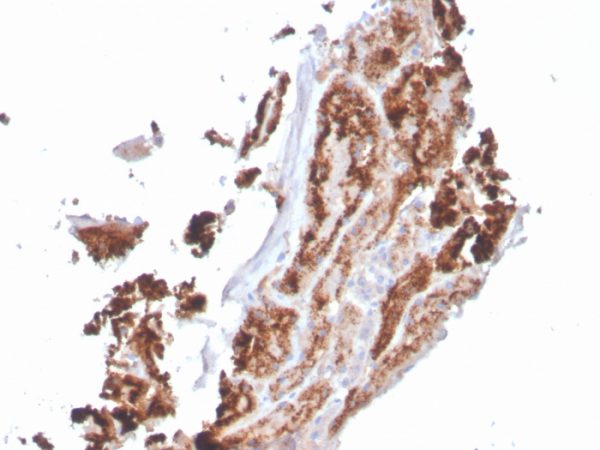

Formalin-fixed, paraffin-embedded human kidney stained with RBP4 Mouse Monoclonal Antibody (RBP4/4049).

Retinol (Vitamin A) is transported in the blood bound to its carrier protein, retinol-binding protein (RBP), also designated plasma retinol-binding protein (PRBP) or RBP4. A member of the lipocalin family, RBP conveys retinol from stores in the liver to peripheral tissues. In plasma, RBP binds transthyretin (TTR, formerly called prealbumin) to prevent glomerular filtration of low molecular weight RBP in the kidneys. The stability of this complex holds diagnostic importance because the molar ratio of RBP:TTR provides an indirect way to indicate marginal Vitamin A deficiency. Vitamin A deficiency blocks the secretion of RBP, resulting in defective delivery and supply to epidermal cells. Originally identified solely as a transporter protein, recent studies correlating increased levels of RBP expression in adipose tissue with Insulin resistance have generated research into the possible roles the protein may play in the pathogenesis of type 2 diabetes and obesity.